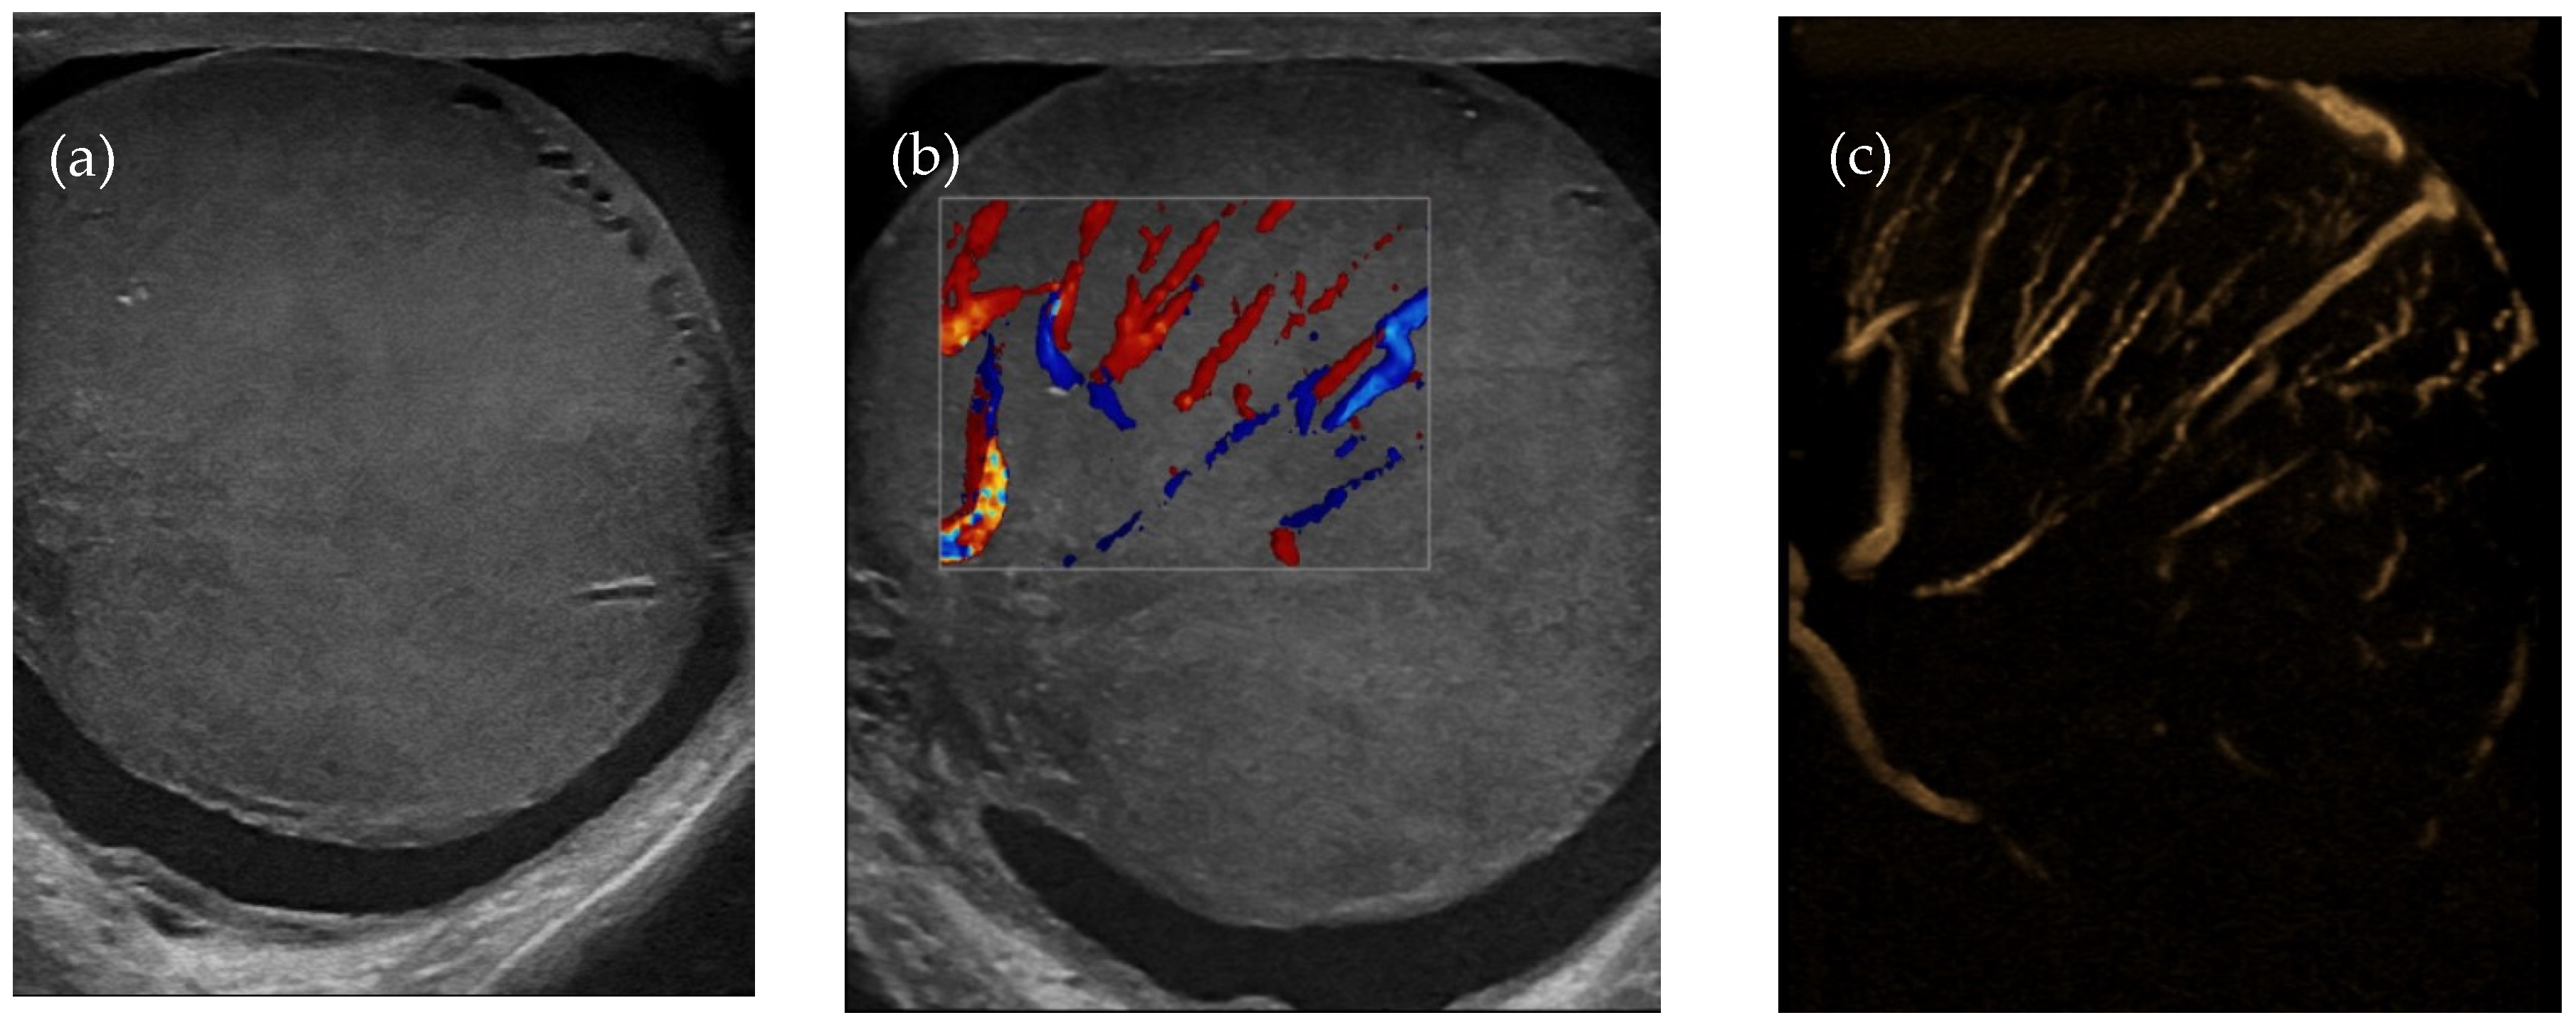

Testicular ultrasound showed an enlarged left testicle of approx. 63/55 mm (Figure 2a), with inhomogeneous diffuse infiltrated echo structure and alternating hypoechoic areas, vascularized in Doppler and B-Flow (Figure 2b), without specific intraparenchymal masses detectable by ultrasound. Transonic peri-testicular fluid was approx. 7 mm diameter (Figure 2c).

Figure 2.

Axial ultrasound section of the left testicle: (a) increased volume, inhomogeneous echo structure, alternating hypoechoic areas; (b) vascular signal present in Doppler; (c) vascular signal present in B-Flow.